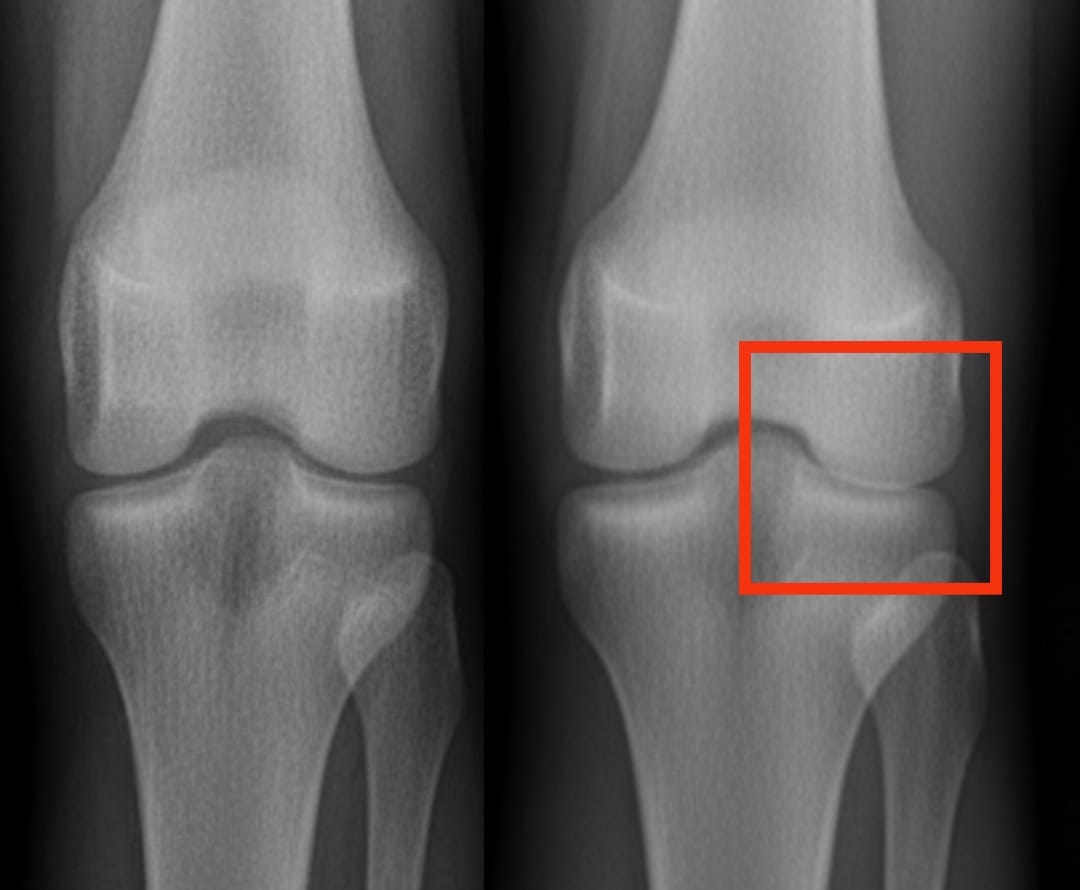

يصيب التهاب مفصل الركبة مئات الملايين من الأشخاص في جميع أنحاء العالم. يتميز بتآكل تدريجي للغضروف، مما يؤدي إلى الألم وصعوبة الحركة. من بين الحلول المقترحة، أثارت حقن بلازما الغنية بالصفائح الدموية اهتمامًا متزايدًا. يستخدم هذا العلاج دم المريض نفسه، مركزًا بالصفائح الدموية، لتحفيز إصلاح الأنسجة وتقليل الالتهاب.

قارنت تحليلات حديثة فعالية بلازما الغنية بالصفائح الدموية بفعالية حقن أخرى شائعة: حمض الهيالورونيك والكورتيكوستيرويدات والدواء الوهمي الملحي. أظهرت النتائج أن بلازما الغنية بالصفائح الدموية تحسن الألم والحركة بشكل ملحوظ بعد ستة أشهر، مع فوائد تستمر حتى عام كامل. هذه التحسينات أكثر وضوحًا مقارنة بحمض الهيالورونيك أو الكورتيكوستيرويدات، وأفضل بكثير من الدواء الوهمي.